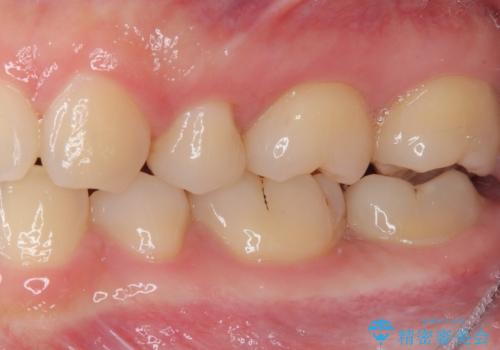

奥歯に物が挟まる セラミックインレーでのむし歯治療

- 食事の度に物が挟まるとのことで来院された患者様です。

目視でも欠損が認められ、レントゲン写真からもむし歯が認められる状態でした。

患者様と相談の上、セラミックインレーで精密な修復治療を行うこととしました。

精密な型取りと、ラバーダム防湿下での接着操作により、歯と詰め物の隙間を最小限にとどめることができ、良好な長期予後が期待できます。